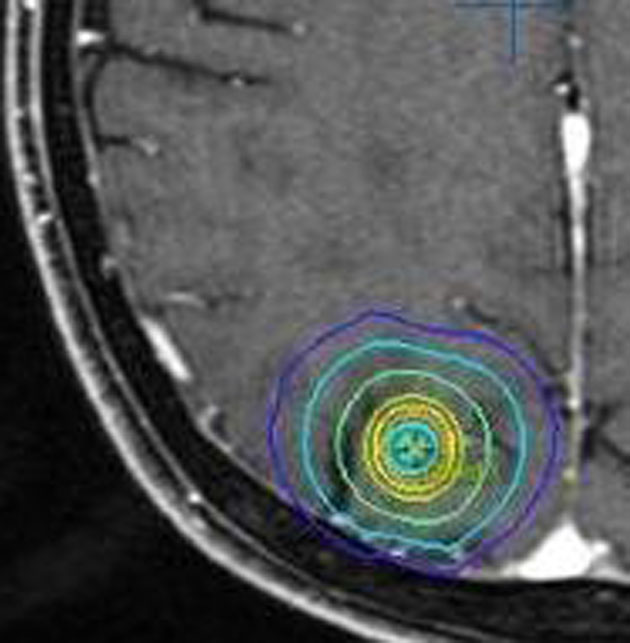

放射線外科 SRS の治療計画です。左側のとても小さな脳転移にたいして,中心線量25グレイ,辺縁線量20グレイの計画です。黄色の線より外にはほとんど放射線が入らない治療です。でも周辺脳が全く被曝しないわけではありません。